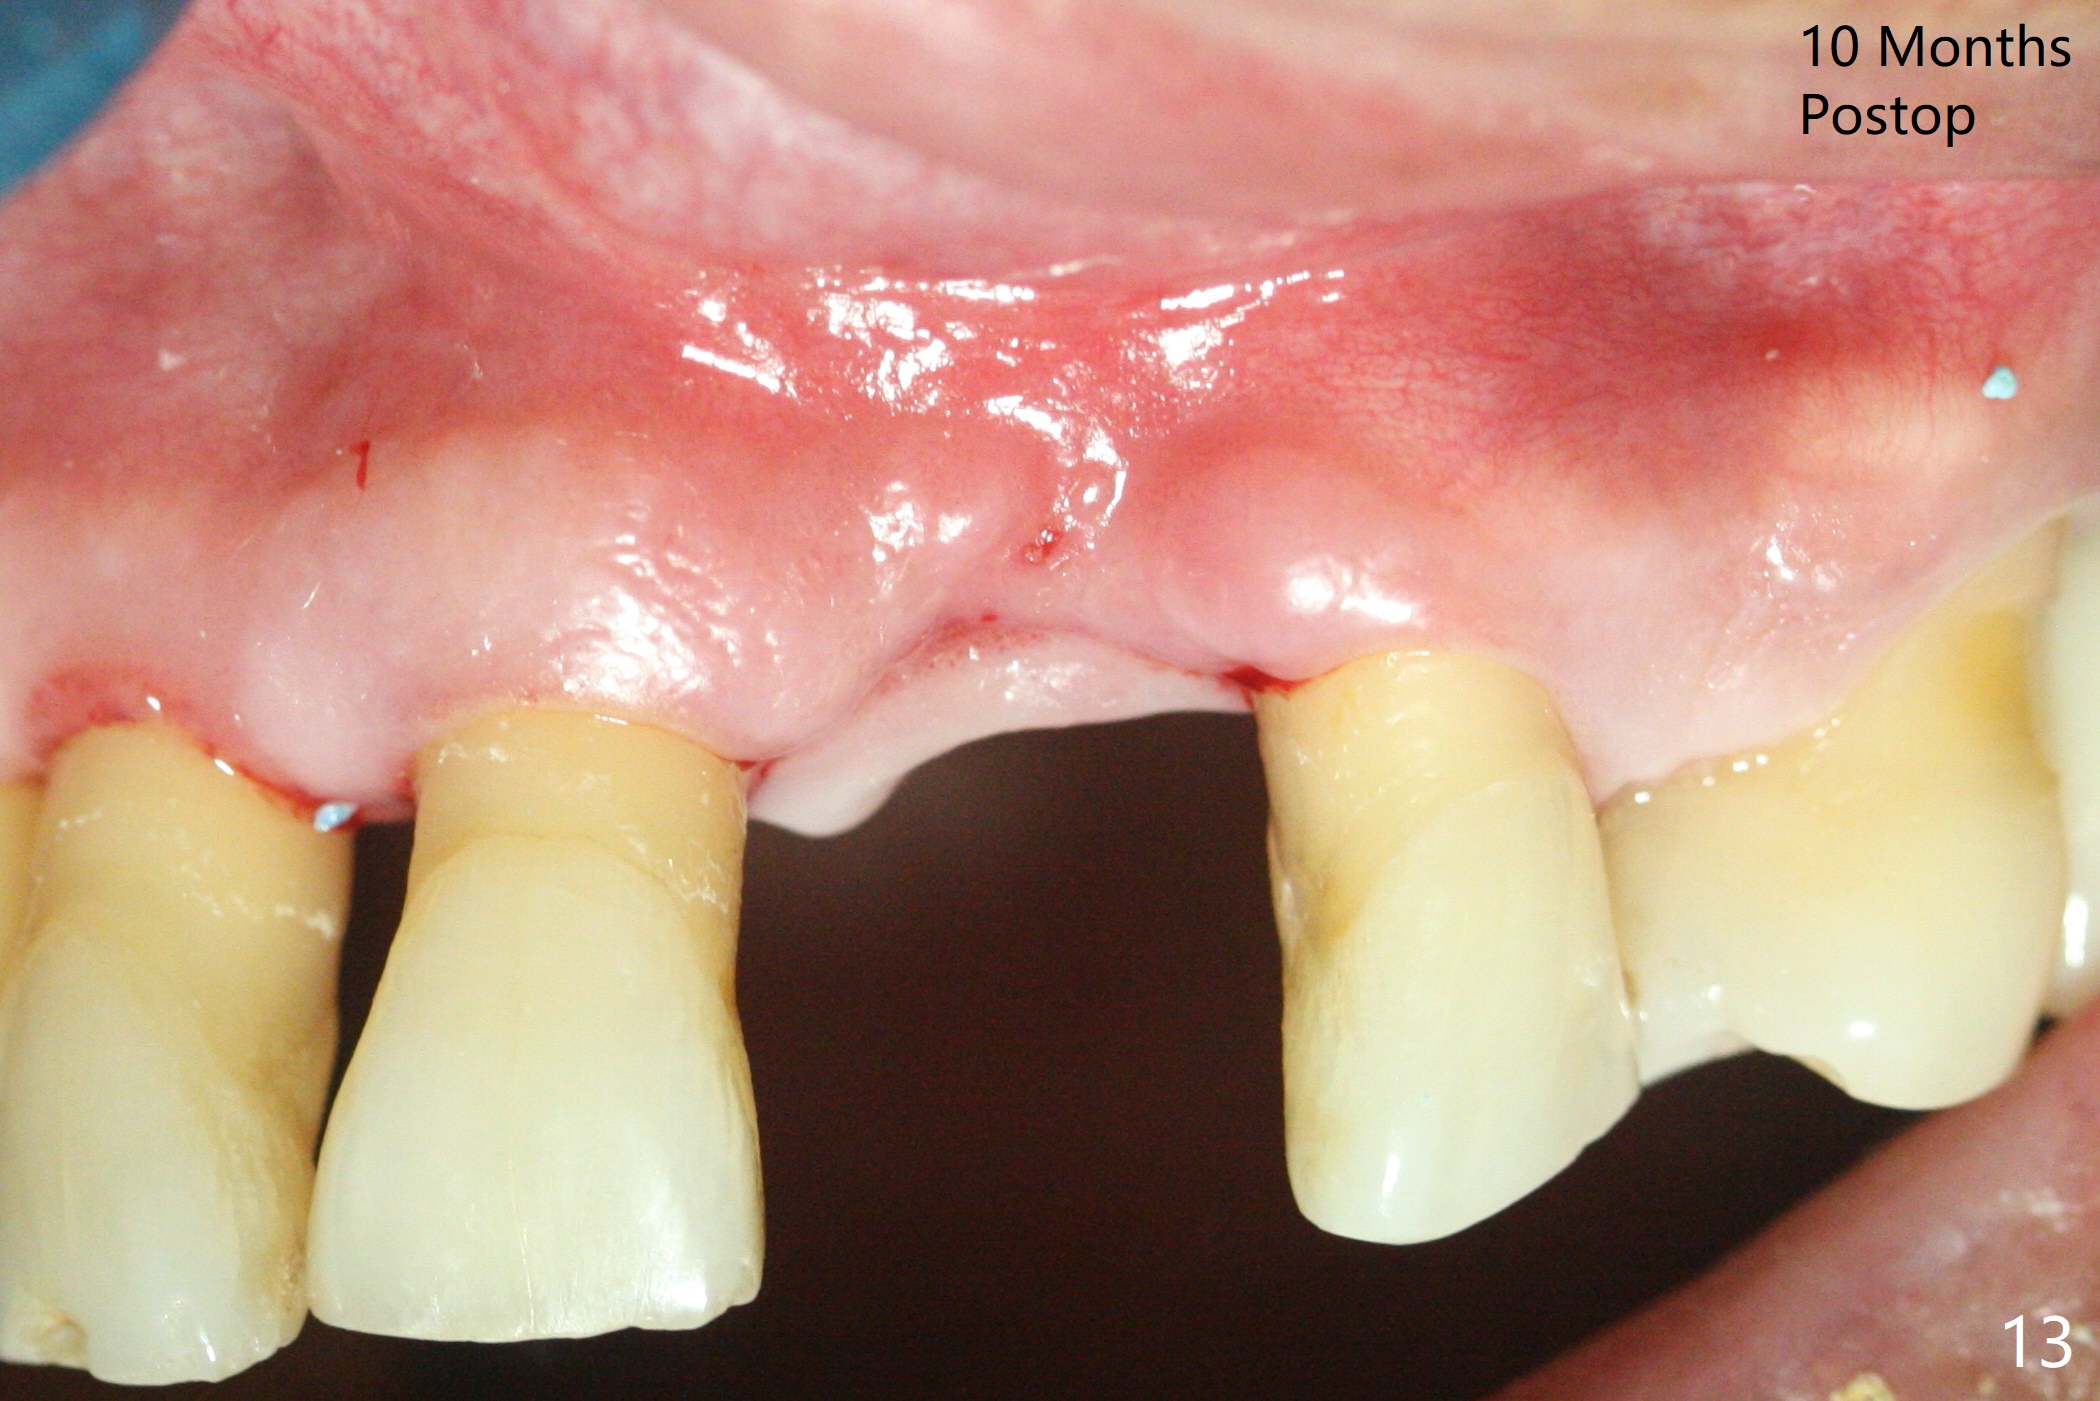

A 67-year-old man requests extraction of the loose tooth #9 (Fig.1). After extraction, the labial plate is found to be missing. With incision, allograft is kept in place with a 12x24 mm anterior narrow Cytoplast and 4-0 Chromic gut suture (Fig.2). Periodontal dressing dislodges in 2 days. The wound dehisces transversely 5 days postop (Fig.3 arrows), whereas the wound was open buccopalatal when the sutures were placed. Probably due to extensive dissection, the erythematous mucosa is large (Fig.4), although asymptomatic. When X-ray shows V-shaped bony defect (Fig.1 (PA), 5 (Pan), 6 (CT)), do not dissect the overlying thin buccal gingiva, which is most likely to dehisce. In fact immediate implant with guide appears to be more conservative, since there is no pressure against the buccal gingiva (Fig.7,8). To be more ideally, the implant could be placed more coronally, longer (13 mm instead of 11.5, Fig.9,10) and narrower (3.5 mm instead of 4.0 mm, Fig.11 (red circles: bone graft)).